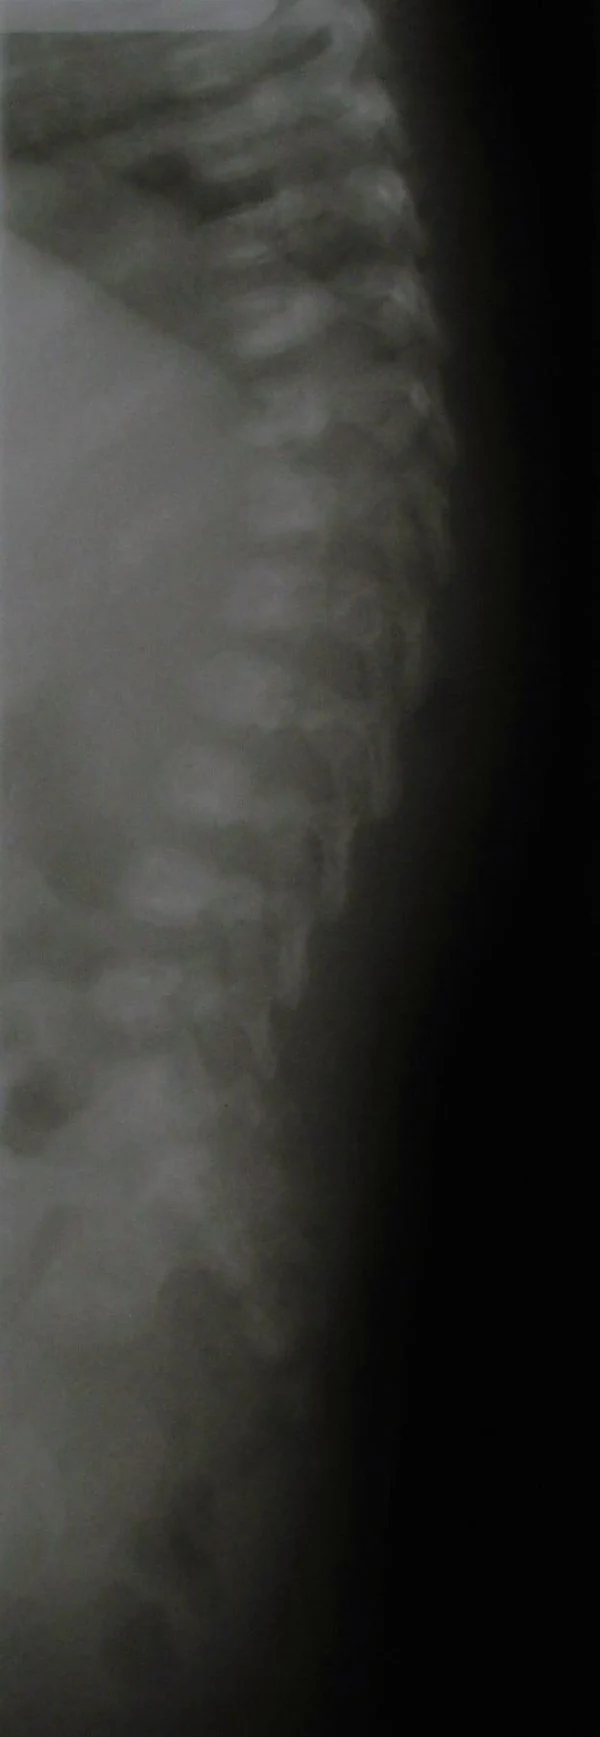

В качестве примера приведены 2 случая хирургического лечения новорожденных с врожденными опухолями головного мозга и позвоночного канала. У новорожденной девочки опухоль (хориодпапиллома) располагалась в области треугольника правого бокового желудочка (рис. 28 а, б). В возрасте 2-х недель жизни опухоль удалена. По данным МРТ головы с внутривенным введением контрастного препарата выполненной через 2 дня после операции опухоль удалена тотально (рис. 28 в). Послеоперационных осложнений не наблюдалось. У второго пациента 2-х нед. жизни врождённая опухоль (нейробластома) располагалась в позвоночном канале на уровне Th10-L3 позвонков (рис. 29 а) и распространялась в забрюшинное пространство. Клиническая картина заболевания складывалась из нижнего вялого парапареза и нарушения функции тазовых органов. Во время операции остистые отростки Th 11-L3 позвонков рассечены по средней линии. Дужки 6 данных позвонков надломлены и разведены в стороны. Опухоль располагалась экстрадурально, отделена от дорзальной поверхности дурального мешка и корешков спинно-мозговых нервов, после чего полностью удалена из позвоночного канала. Половинки дужек позвонков сведены к средней линии и сшиты между собой. Опухолевый узел в забрюшинном пространстве через 2 нед. удален онкологами. Через год после операции по данным МРТ рецидива опухоли нет (рис. 29 б). При спондилографии дефектов задней стенки и деформаций позвоночника не выявлено (рис. 29 в). Мальчик ходит, мочу и кал удерживает.